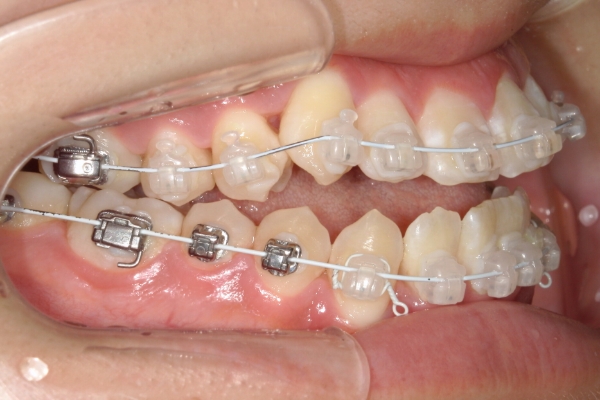

BEFORE

治療前

PROCESS

3か月

AFTER

治療後

骨格的に下あごが前下方に長いことが原因で、受け口、開咬(前歯が当たらない)の症状がでていました。また下あごが右にずれており、その影響で上下の歯列正中(真ん中)の大きなずれも生じていました。顎変形症手術も選択肢の一つでしたが、患者さまの希望もあり、下顎左側小臼歯の抜歯をして通常の歯列矯正で治療をしました。

治療後は、前歯、奥歯の噛み合わせが整い、上下の歯列の真ん中が一致しました。歯列全体のアーチも安定し、機能面・審美面のどちらも大きく改善されました。